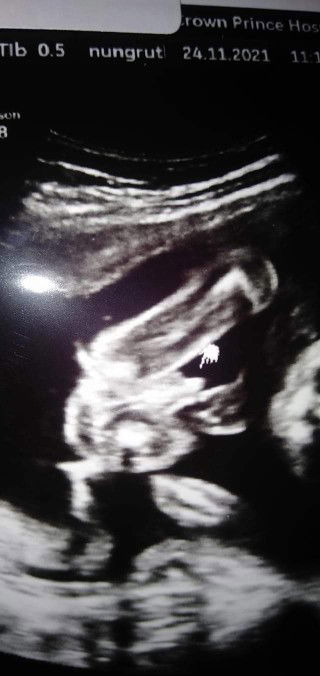

เพศลูก ในภาพเป็นหญิงหรือชายค่ะ

แบบนี้ผู้ชายหรือผู้หญิงค่ะเเม่ดูไม่เป็น ช่วยบอกหน่อยค่ะ 😁😊 (ในใจอยากได้ผู้ชายมากค่ะ)#ขอบคุณสำหรับคำตอบค่ะ #ท้องแรกคะ #ขอบคุณล่วงหน้านะคะ